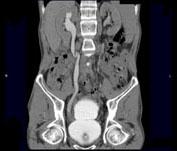

问题 男,53岁,无痛性血尿2个月余,CT扫描如图示,下列说法正确的是 ( )

选项 A、考虑为输尿管移行细胞癌 B、考虑为输尿管内血块 C、软组织肿块边缘毛糙不平 D、其上方的输尿管扩张 E、右侧输尿管下段可见沿输尿管走行的软组织肿块影

答案 ACDE